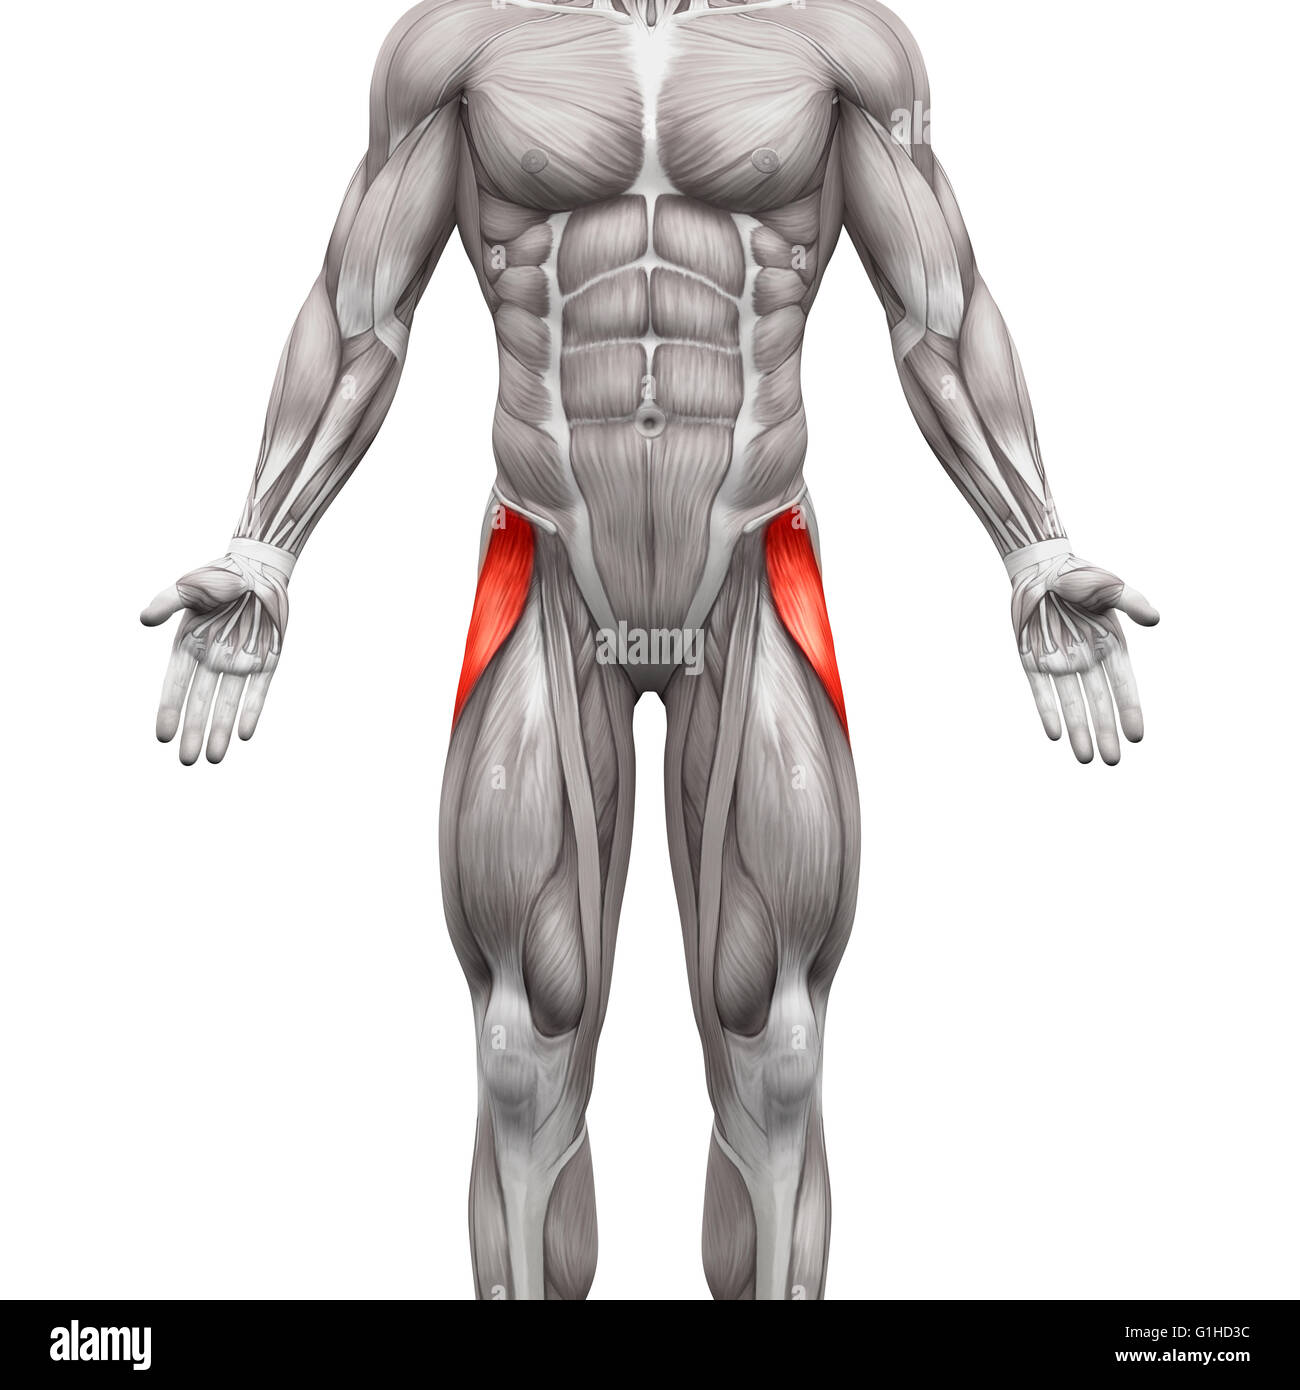

Tensor Fasciae Latae Muscle - Anatomy Muscles isolated on white - 3D illustration Stock Photohttps://www.alamy.com/image-license-details/?v=1https://www.alamy.com/stock-photo-tensor-fasciae-latae-muscle-anatomy-muscles-isolated-on-white-3d-illustration-104260336.html

Tensor Fasciae Latae Muscle - Anatomy Muscles isolated on white - 3D illustration Stock Photohttps://www.alamy.com/image-license-details/?v=1https://www.alamy.com/stock-photo-tensor-fasciae-latae-muscle-anatomy-muscles-isolated-on-white-3d-illustration-104260336.htmlRFG1HD3C–Tensor Fasciae Latae Muscle - Anatomy Muscles isolated on white - 3D illustration